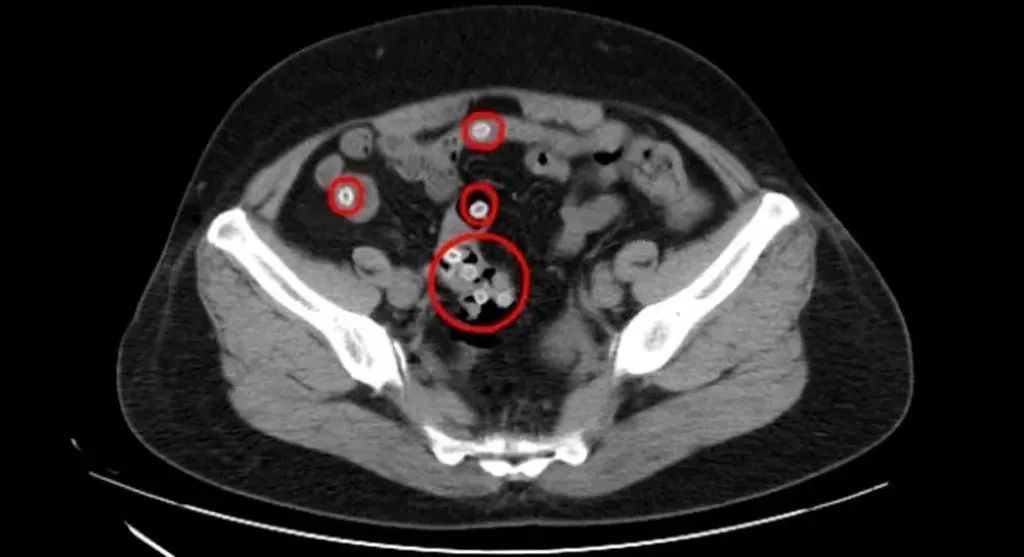

△CT影像显示,患者肠道内有不少杨梅核滞留

CT影像显示,王阿姨的肠内存在多处类圆形高密度影,密密麻麻的圆圆小白点正是滞留在肠道内的杨梅核,这是导致患者腹痛不止的罪魁祸首。